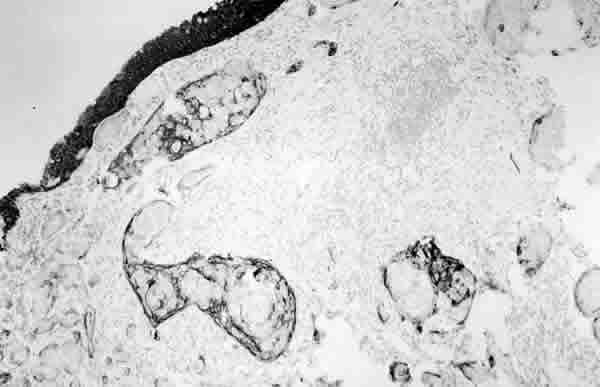

Figura 3

INMUNOREACTIVIDAD PARA LA CITOQUERATINA. OBSÉRVESE COMO LAS CÉLULAS TUMORALES QUE SE DISPONEN EN NIDOS ASÍ COMO EL EPITELIO NORMAL SE TIÑEN DE OSCURO, QUE CORRESPONDE A LA TINCIÓN MARRÓN CON PEROXIDASA (PEROXIDASA).